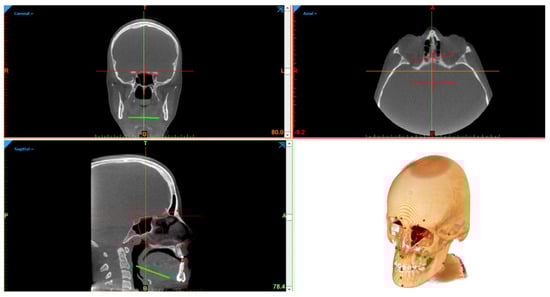

Eighteen cephalometric landmarks were defined using Mimics 22.0 (Materialise, Leuven, Belgium), according to the classical Steiner methods [] (Figure 1).

Figure 1.

Figure representing the full 3D cephalometry multi-planar vision and three-dimensional reconstruction.

N (Nasion), S (Sella), Ba (Basion), A (Point A), B (Point B), ANS (Anterior Nasal Spine), PNS (Posterior Nasal Spine), Me (Menton), UI (Upper Incisor), and LI (Lower Incisor).

- Four paired landmarks divided into right and left:

Sor (Supra Orbital), Mx (Maxillar), Cd (Condylion), and Go (Gonion). A total of 36 measurements between them were automatically calculated by the function of the software measurements and analysis (21 linear, of which 7 were paired, unit: mm, and 15 angular, of which 5 were paired, unit: degrees):